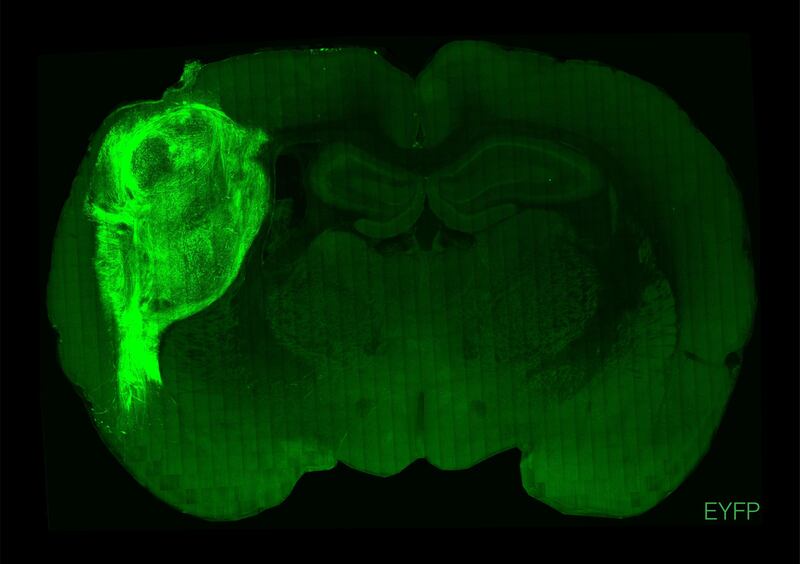

A transplanted human organoid labeled with a fluorescent protein in a section of the rat brain.

Stanford University“Psychiatric disorders are a huge burden to society,” Pasca said during a press briefing. “I believe we have a moral imperative to find better models to study these conditions.”

In the study, Pasca and his team transplanted human-derived brain organoids into the cerebral cortices of over 80 newborn rats and let the rats develop normally over the course of the next eight months. They found that the human neurons grew to take up a third of a hemisphere in the rat’s brains—each neuron was about six times larger than it would have been if grown in a petri dish, like a typical organoid. The transplanted neurons also grew more connections and had a greater concentration of negative ions within their membranes, more closely mimicking the human brain compared to petri dish organoids.